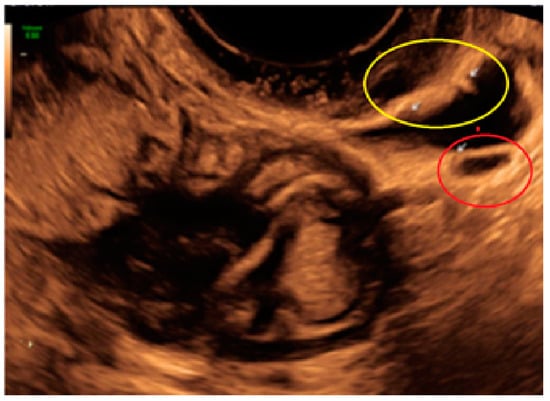

- The presence of hypoechogenic associated tissue (hypoechoic areas surrounding a small cyst area; we called this a “hat”). This tissue does not protrude or invaginate the peritoneal surface.

- The lesion may be convex, protruding from the peritoneal surface into the peritoneal cavity (we called this “bulging”), or it may appear as a concave defect in the peritoneum (we called this a “pocket”).